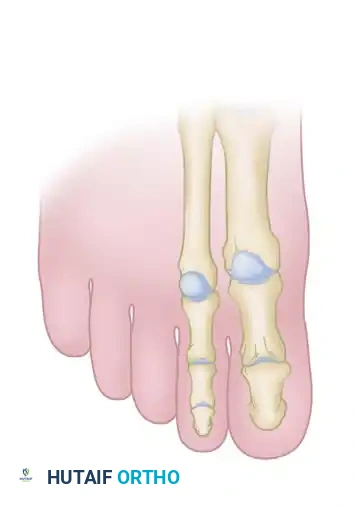

Clawing of the great and lesser toes is a complex multi-planar deformity characterized by hyperextension at the metatarsophalangeal (MTP) joint and flexion at the proximal interphalangeal (PIP) and distal interphalangeal (DIP) joints. In the hallux, the deformity manifests as MTP hyperextension and interphalangeal (IP) joint flexion. This condition is frequently encountered in the setting of neuromuscular disorders (such as Charcot-Marie-Tooth disease), intrinsic minus foot conditions, rheumatoid arthritis, or as a sequela of compartment syndrome and isolated plantar fascia release.

The primary pathoanatomy involves an imbalance between the strong extrinsic extensors (Extensor Hallucis Longus [EHL], Extensor Digitorum Longus [EDL]) and the weakened or overpowered intrinsic musculature (lumbricals and interossei). When the intrinsic muscles fail to flex the MTP joints, the extrinsic extensors draw the proximal phalanx into rigid dorsiflexion. Consequently, the extrinsic flexors (Flexor Hallucis Longus [FHL], Flexor Digitorum Longus [FDL]) exert an unopposed flexion force on the interphalangeal joints, exacerbating the clawed posture.

4. Management of the Hallux Interphalangeal Joint

If the IP joint of the great toe remains rigidly flexed, it must be addressed to prevent a "cock-up" deformity postoperatively.

5. Correction of the Second Toe

Return to the first intermetatarsal space incision to manage the second toe MTP joint. Lengthen the EDL, tenotomize the EDB, and perform a dorsal capsulotomy and collateral ligament release at the second MTP joint, mirroring the steps performed on the hallux.

Next, address the rigid PIP joint contracture of the second toe: